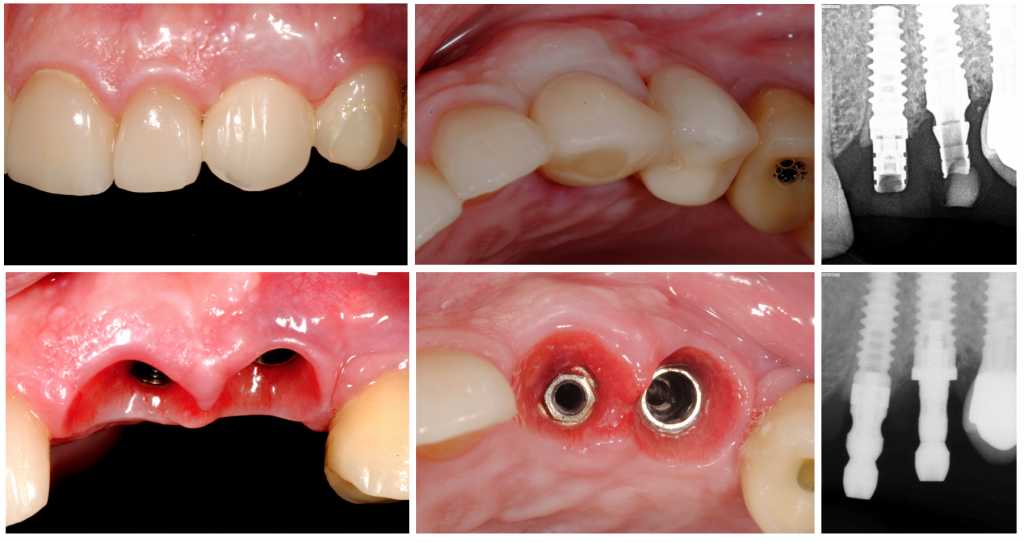

Ocho meses después, se sustituyó la corona provisional por una corona tradicional de circonio, mostrando una sorprendente arquitectura gingival, que se consideró inmutable después de una 6th, 18th, y 24th período de seguimiento del mes.

En este informe de caso, se demostró que la técnica Socket Shielde con la colocación inmediata del implante, según lo informado por HÜrzeller 2010, preserva la placa cortical bucal y se pueden observar tejidos periimplantarios sanos, demostrando ser una de las estrategias de preservación de crestas más conservadoras para los contadores óseos y la preservación de la arquitectura gingival, y pensada para obtener una apariencia más estética. resultado final.